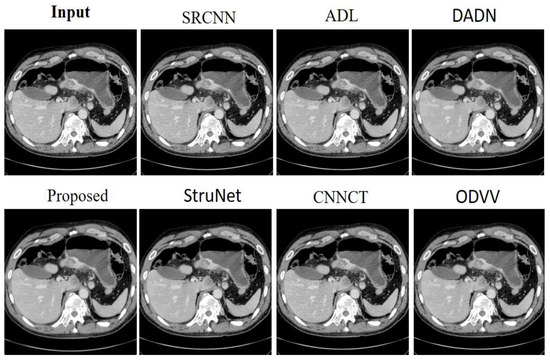

Figure 4 provides a visual comparison of denoising methods on an abdominal CT image from the AAPM dataset. The input image serves as the baseline, displaying the raw scan with its inherent noise and details. The SRCNN [33] method shows a little noise reduction, but the image remains relatively grainy. The ADL [15] approach appears to reduce noise while maintaining a good level of detail, though some structures are not as crisp. DADN [22] further smoothens the image, with noticeable improvement in noise suppression, yet at the risk of losing fine details. The lower row begins with the proposed method, which visibly enhances the image by reducing noise substantially without compromising the integrity of the anatomical structures. The clarity of internal features is markedly improved, making this method potentially valuable for clinical evaluation. StruNet [31] also offers a cleaner image, but with a slight blur that could obscure finer details. CNNCT [13] rendition is cleaner than the input but does not reach the level of noise reduction achieved by the proposed method. Lastly, ODVV [32] provides a denoised image, yet some areas appear over-smoothed, which could be problematic for diagnostic purposes. The proposed model stands out with its balance between noise reduction and detail preservation, suggesting its superior capability for producing diagnostically useful images.

Figure 4. Results achieved by the evaluated noise-reduction models on the AAPM dataset.